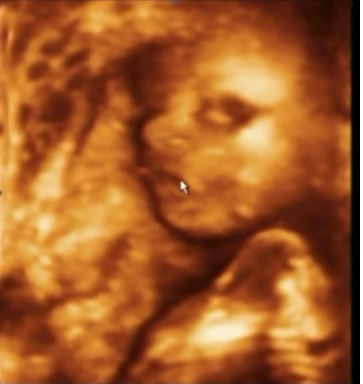

УЗИ в Арт Мед 21 неделя

УЗИ, КТГ, доплерВот наконец то настал этот долгожданный день и мы сделали Узи в Арт Мед у специалиста эксперт класса Мазырко М. Все у нас хорошо. Сделали несколько снимочков в 2D и 3D. И самое долгожданное событие - у нас будет принцесса. Можно имя подбирать и вещички прикупать!!!

Узистка начала осмотр с головы и когда спустилась ниже и начала объяснять, что вот мол бедренная кость я четко поняла, что это девочкаи начала улыбаться.Когда она промолвила, что это у нас девочка я уже в этом не сомневалась - так четко было видно.